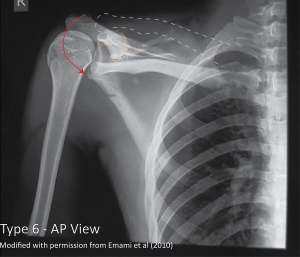

Grade VI

The clavicle is inferiorly displaced behind coracobrachialis and biceps tendons.